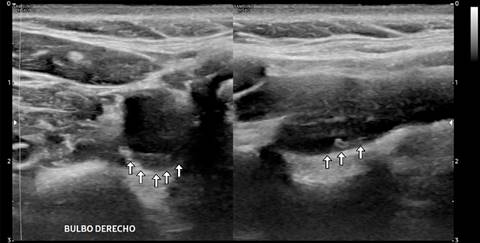

Femenino de 40 años con ataque isquémico transitorio (AIT), en la que se efectuó ultrasonido y angiotomografía que mostraron banda carotídea ipsilateral. La displasia fibromuscular atípica del bulbo o banda carotídea es una patología no ateromatosa implicada en la aparición de infartos cerebrales. La banda carotídea se define como un defecto de llenado lineal en forma de estante en la cara posterior del bulbo de la arteria carótida interna mediante angiotomografía (Figura 1) y/o ultrasonido (Figuras 2 y 3), se reconoce cada vez más como una causa de accidente cerebrovascular criptogénico y/o AIT recurrente, pero la evidencia sigue siendo escasa. Se observa en ambos géneros, con distribución 2:1 a favor del femenino y mayor incidencia en personas de color; cuando son bilaterales (60%) presenta mayor longitud en el lado ipsilateral sintomático que en el contralateral (3-4.5 mm vs 1.85-2.9 mm), observando trombos superpuestos hasta en 30% de los casos con banda carotídea sintomática. A pesar de la recurrencia y gravedad de los accidentes cerebrovasculares originados por embolización asociada con banda carotídea, no existen recomendaciones sobre la mejor estrategia para su manejo; el tratamiento con agentes antiplaquetarios previene la aparición de accidentes cerebrovasculares, pero el tratamiento radical sigue siendo quirúrgico y/o endovascular.

Figura 2: A) Imagen Doppler color y espectro que demostraron cambios en la dirección del flujo vascular adyacente a la protrusión intimal y de flujo turbulento en ambas direcciones. B) Imagen por ultrasonido 2D longitudinal que demostró en la pared posterior del bulbo carotídeo derecho una banda isoecogénica intimal que protruye hacia el lumen arterial.